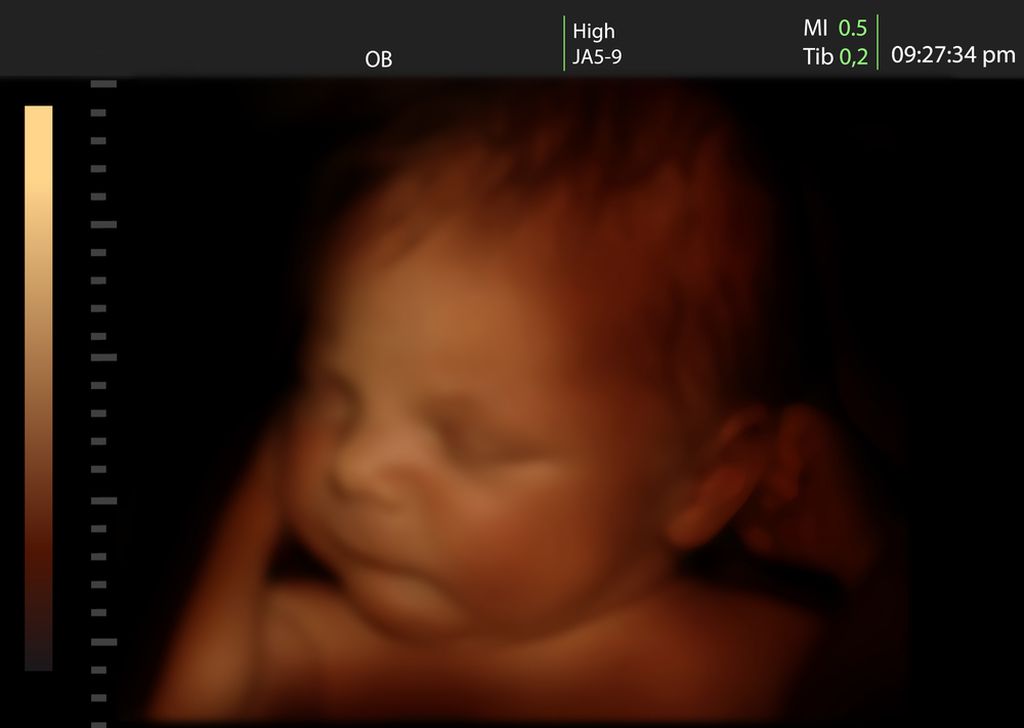

Μια επαναστατική συσκευή που εφευρέθηκε στις ΗΠΑ επιτρέπει στους μέλλοντες μπαμπάδες να νιώσουν το παιδί που κυοφορεί η γυναίκα τους να κινείται μέσα στη δική τους κοιλιά! Αποτελείται από δύο ζώνες, τις οποίες φορούν η έγκυος και ο σύντροφός της. Οι ζώνες που μοιάζουν με εκμαγείο κοιλιάς σε κατάσταση εγκυμοσύνης, συνδέονται μέσω ηλεκτροδίων και επιτρέπουν στο μελλοντα μπαμπά να νιώσει στο δικό του σώμα τις κινήσεις του εμβρύου ακριβώς τη στιγμή που αυτό κινείται στη μήτρα της γυναίκας. Τη συσκευή δημιούργησαν η αμερικάνικη εταιρεία βρεφικών ειδών Huggies, σε συνεργασία με την Ogilvy & Mather Argentina, αλλά δεν έχει διευκρινιστεί ακόμα εάν και πότε πρόκειται να βγει στο εμπόριο. Δείτε το σχετικό βίντεο:

Βίντεο: Τώρα και οι μπαμπάδες μπορούν να νιώσουν το έμβρυο!